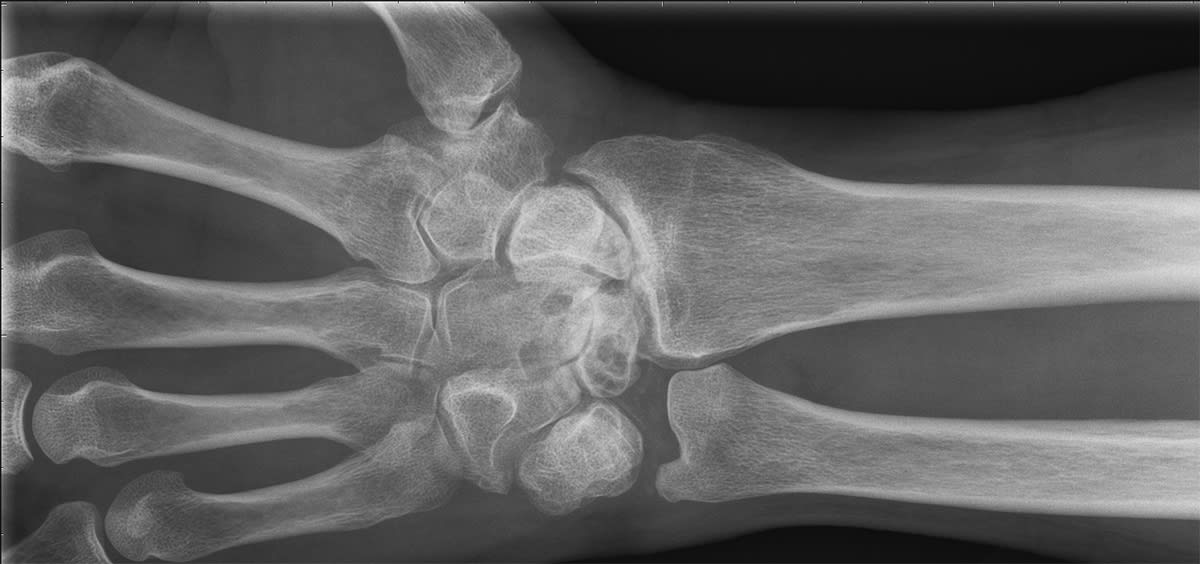

Vid handledsartros är det vanligt att behandlingen inriktas på att eliminera kontakt mellan de leder som ger upphov till besvären. De vanligaste metoderna är handledsprotes, partiell steloperation mellan mindre leder i handleden eller komplett steloperation av handleden. Samtliga dessa metoder kan ge smärtlindring, men ger samtidigt olika grader av nedsatt rörlighet som en direkt följd av operationen. Efter ett sådant ingrepp behöver handleden dessutom vara gipsad i flera veckor innan patienten får börja belasta den.

Handledsdenervation innebär att man bevarar handledens skelettanatomi och istället behandlar smärtan genom att skära av de nervändar som leder smärtimpulserna vidare från handleden. Dessa har ingen motorisk funktion och att de skärs av medför ingen förlust av handfunktionen. Handens sensibilitet i övrigt förblir också oförändrad. Behandlingen förbättrar smärttillståndet helt eller delvis utan att försämra rörligheten i leden. Patienten får ett mjukt förband och kan, till skillnad från en steloperation, börja använda handen direkt med lätt belastning.